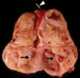

Esophageal leiomyomatosis

A leiomyoma, also known as fibroids, is a benign smooth muscle tumor that very rarely becomes cancer (0.1%). They can occur in any organ, but the most common forms occur in the uterus, small bowel, and the esophagus. [Source: Wikipedia ]